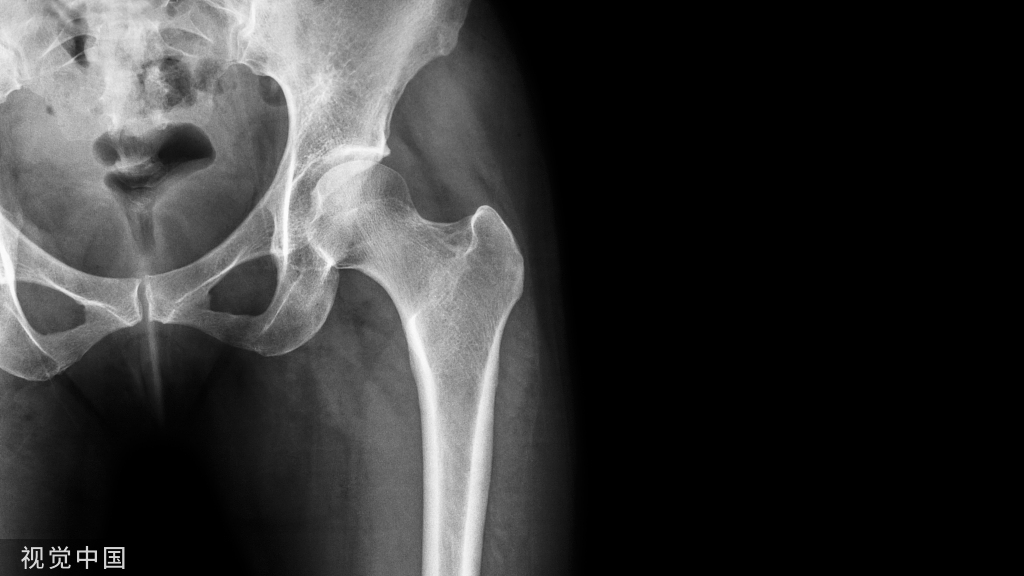

原发性骨质疏松症的发病机制遗传因素主要影响骨骼大小、骨量、骨微结构和力学特性等。人类个体间骨量的差异50%~80% 由遗传因素决定。目前利用全基因组关联分析(genome-wide association study,GWAS)已鉴定出了近 600 个基因座位与骨密度、骨质疏松症和骨折相关,大约可以解释人类 20% 的骨密度差异。

通过 GWAS 发现的具有已知功能的易感基因,主要分布在四条骨代谢生物学通路上:1.WNT信号通路(LRP5、SOST、WNT10B、WNT16、SFRP1、FOXC2、LRP4、GPR177 和 CTNNB1);2.RANK信号通路(RANKL、RANK 和 OPG);3.维生素D信号通路(VDR 和 DBP);4.雌激素信号通路(ESR1、ESR2 和 CYP19A1)。

GWAS 新发现的众多易感基因有望揭示骨代谢的新生物学通路。

通观骨质疏松症发病机制,遗传因素决定着峰值骨量的60~80%,因此,人种和骨质疏松或脆性骨折家族史是重要危险因素;而老龄化和女性绝经及不良生活方式(如缺乏体力活动、低体重、缺少日照、钙和维生素D缺乏、蛋白质摄入不足或过量、吸烟、过量饮酒等)也是重要的危险因素;还有一些影响骨代谢的疾病和药物都以不同的机制导致骨量丢失和骨强度受损,因此,是我们防治骨质疏松症的干预重点。